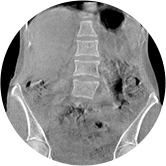

腰椎

精準(zhǔn)診斷

手術(shù)方案規(guī)劃

術(shù)后隨訪(fǎng)